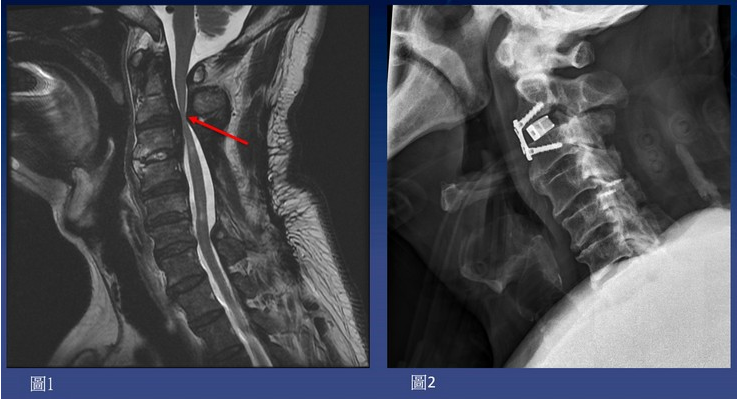

圖:經MRI檢查發現病人的第二、三節頸椎後縱韌帶骨化非常嚴重,受壓迫的神經幾乎扁成一條線。

圖:術前檢查,高位頸椎後縱韌帶骨化,嚴重擠壓脊髓神經(如圖1);醫師精準的用電鑽把骨刺全部磨乾淨,再以骨釘固定及骨融合手術(如圖2)。